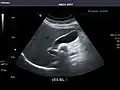

Abdominal ultrasound can be used to diagnose abnormalities in various internal organs, such as the kidneys,[1] liver, gallbladder, pancreas, spleen and abdominal aorta. If Doppler ultrasonography is added, the blood flow inside blood vessels can be evaluated as well (for example, to look for renal artery stenosis). It is commonly used to examine the uterus and fetus during pregnancy; this is called obstetric ultrasonography.[2][3]

Kidneys: Right and left kidneys measure 11.5 cm and 12 cm in length respectively. No hydronephrosis. Small left lower pole kidney cyst.

Left kidney -